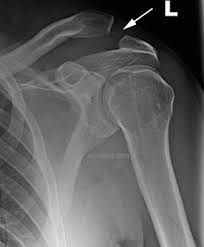

Shoulder separation symptoms vary depending on the degree of injury, but may include: Acute pain at time of injury Pain and swelling over the top of shoulder Bruising Tenderness to the touch Limited mobility in the shoulder Visible bump on top the shoulder A shoulder injury of Grade III will generally be accompanied by pain with any arm motion, causing the patient to support the elbow and hold the arm close to the side.